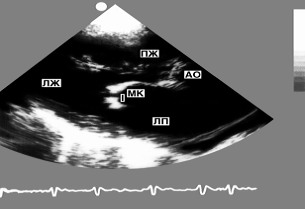

Рис. 8. Двухмерная эхокардиограмма из верхушечного доступа: видны полости всех четырех камер сердца (темные поля) в поперечном сечении, разделенные перегородками и створками атриовентрикулярных клапанов (светлые структуры)